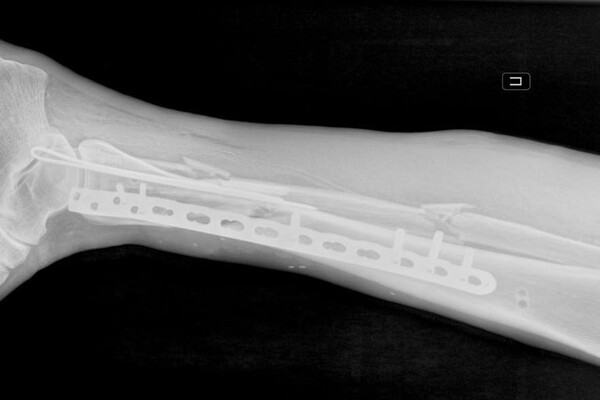

У пострадавшего были диагностированы перелом костей правой голени со смещением, рваная рана бедра и обширная рана левой голени. В больницу мужчину доставили вместе с плугом культиватора. На момент поступления нога была холодной и посиневшей, кровь в конечность не поступала.

«Мы провели срочную операцию, в ходе которой промыли раны и закрепили отломки костей правой голени в анатомически правильном положении с помощью аппарата внешней фиксации. Также восстановили кровоток и устранили сдавление сосудов», — рассказал врач-травматолог-ортопед Игорь Кучерявый.